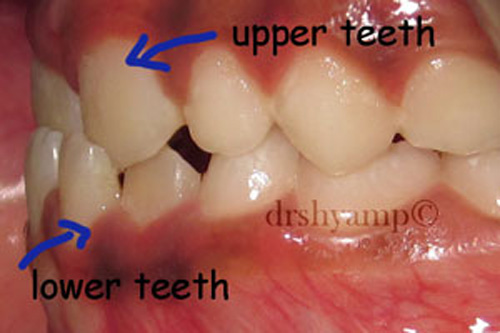

anterior cross bite

-

anterior cross bite

-

anterior cross bite

-

anterior cross bite

Correction of anterior cross bite